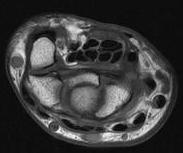

Anatomy

Transverse carpal ligament / TCL

- tuberosities of scaphoid and trapezium laterally

- pisiform and hook of hamate medially

- distal volar wrist crease proximal limit

- Kaplan's line (apex of interdigital fold between thumb and IF) distal limit

Carpal tunnel

- FCR in separate tunnel with FPL separate and below

- median nerve radial to 4 FDS

- IF / LF below MF / RF

- 4 FDP at base

- FPL separate